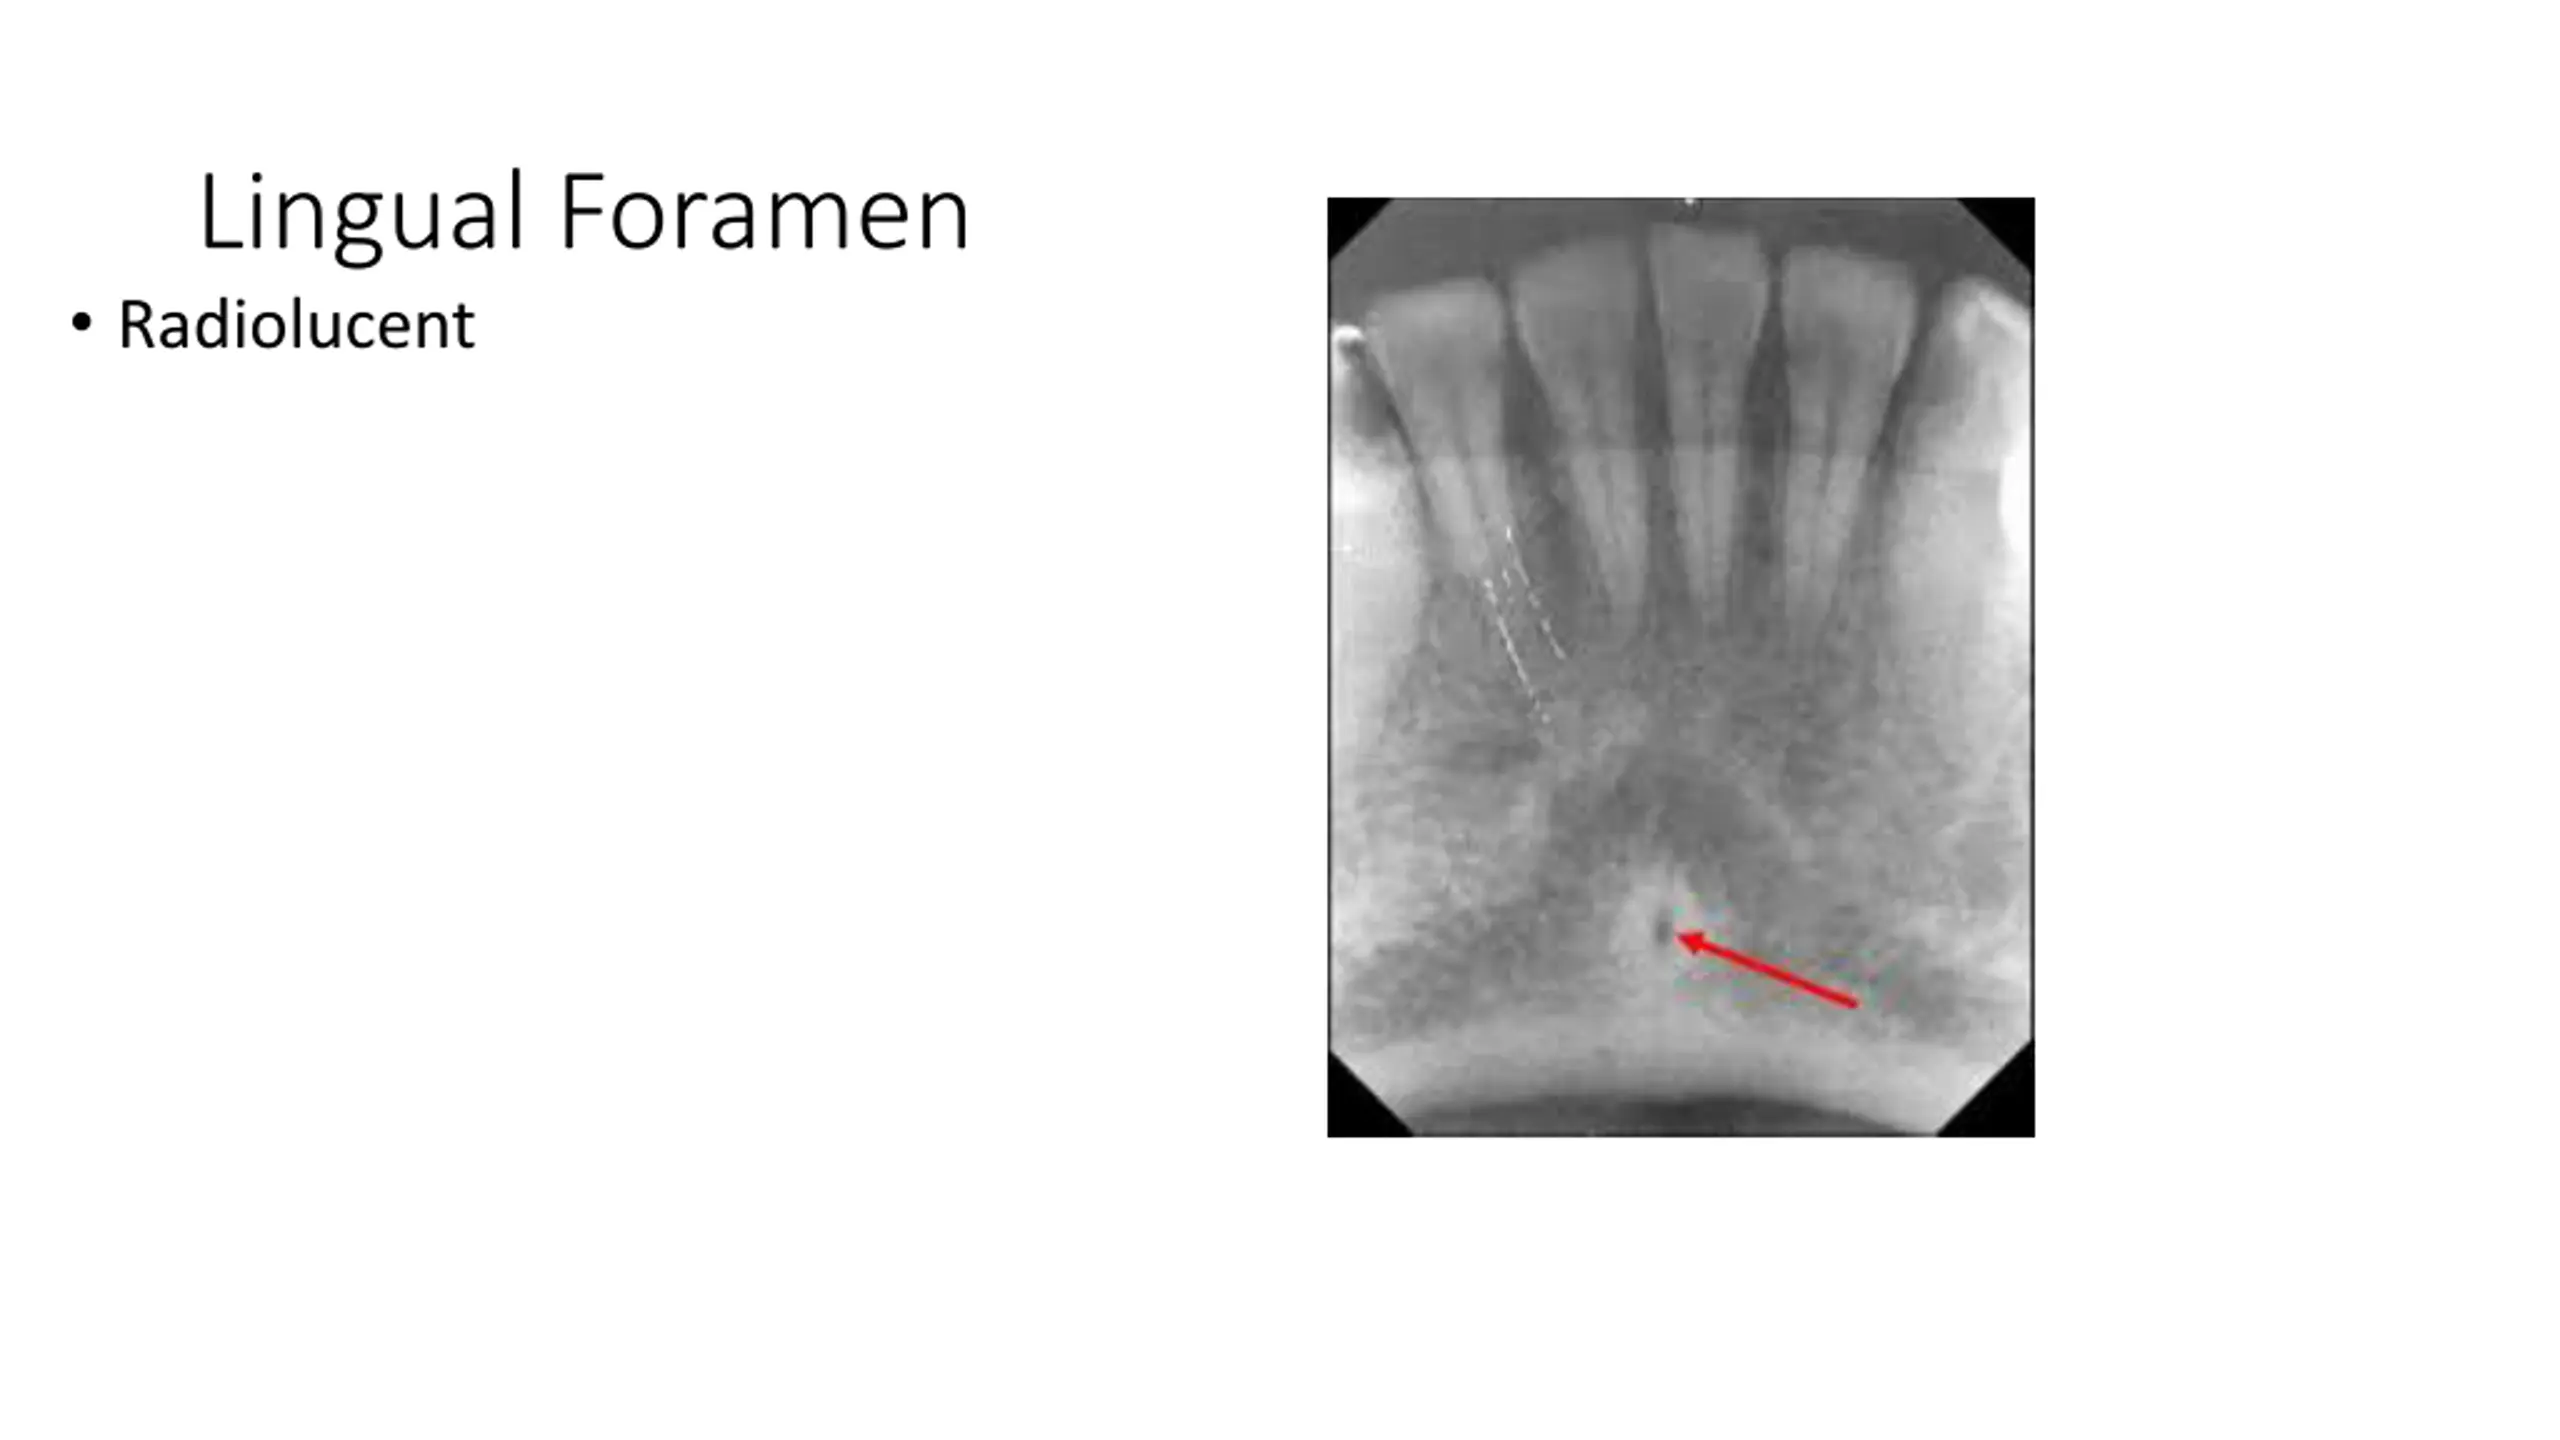

Lingual Foramen Radiolucent